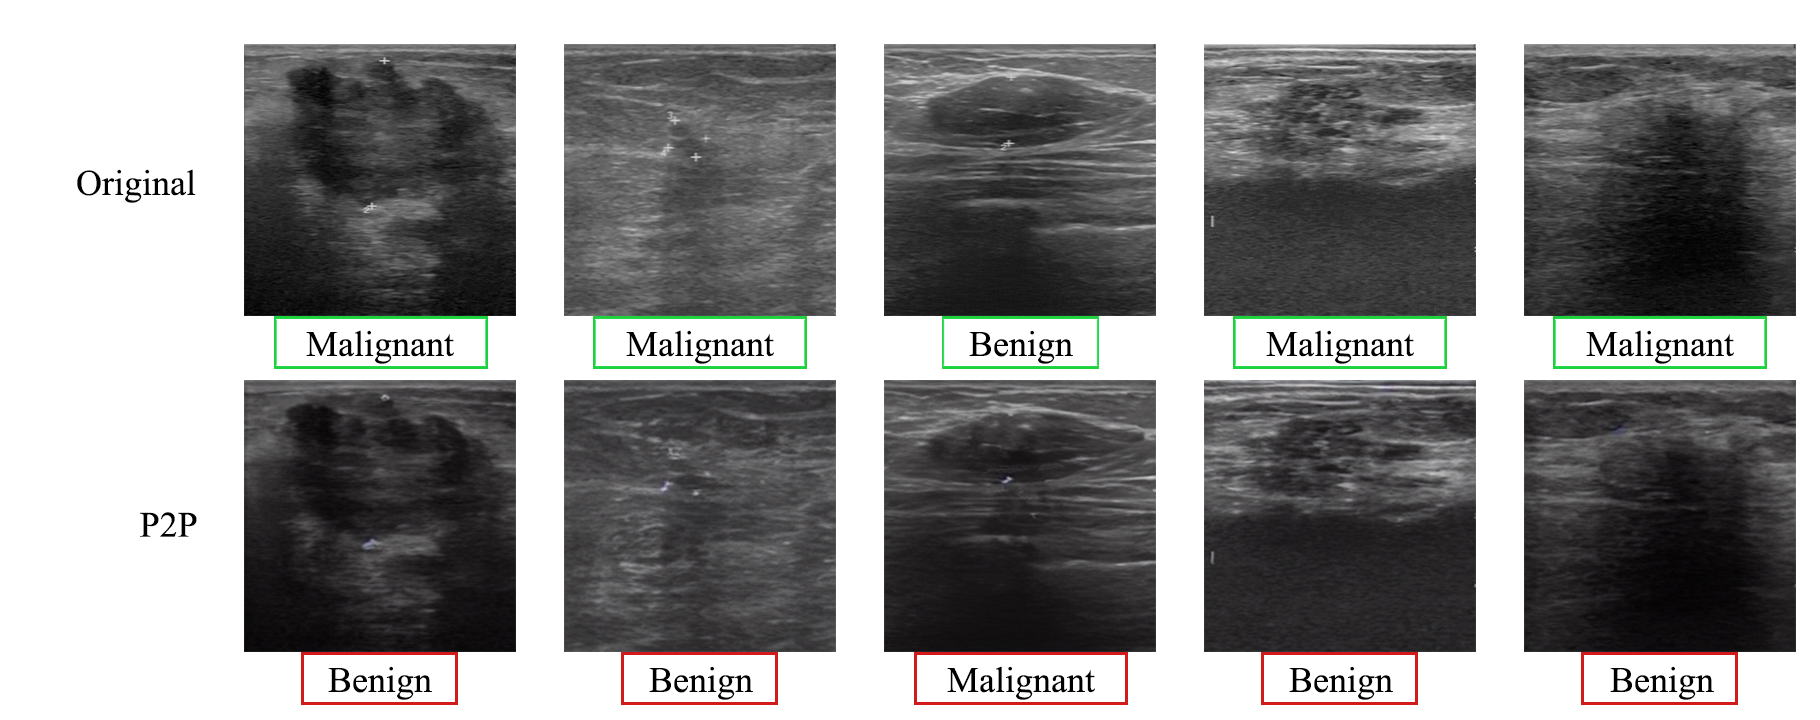

Refer to caption

Figure 4: Comparison of original and P2P-attacked ultrasound images from BUS-BRA Dataset, using DenseNet121 as the classifier. The top row shows the original images with their diagnostic labels, while the bottom row displays the same images after applying the P2P attack. Green boxes indicate the true labels, while red boxes show the labels predicted by the classifier after the attack.

Figure 3 presents visual comparisons of images and adversarial perturbations generated by different attack methods. Notably, our method (P2P) produces attack examples that more closely follow the distribution of the original medical images, resulting in a more natural and less detectable alteration. In contrast, other attack methods, such as FGSM, PGD, and Diff-PGD, introduce high-frequency noise with a distinct ”textured” appearance. This textured noise can make these adversarial examples appear less natural, potentially revealing them as manipulated images, exhibit noisy artifacts. Besides, Fig. 4 shows that the P2P attack successfully changes the diagnostic labels of ultrasound images with minimal alteration to the images’ semantic appearance, demonstrating label vulnerability despite preserved image semantics. Moreover, the t-SNE [54] visualization of clean and attacked image features further confirms the effect of our prompt learning method. Figure 5 compares four attack methods—FGSM, PGD, Diff-PGD, and P2P (Ours)—in terms of how well they blend attack samples with clean data clusters. Diff-PGD shows limited effectiveness, with noticeable separations between attack and clean samples. FGSM and PGD improve blending but still leaves isolated clusters of attack points. P2P achieves the best integration, with attack samples closely interwoven with clean data, indicating superior performance in making adversarial examples indistinguishable from clean data.